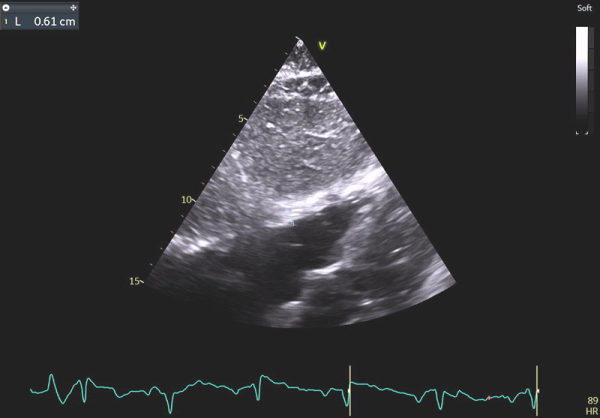

Image 9 : échocardiographie 2D en incidence sous-costale, mesure de l’épaisseur de la paroi du ventricule droit (VD)

En effet, c’était le diagnostic à éliminer en priorité devant les symptômes présentés par la patiente avec un ECG légèrement microvolté et des éléments évocateurs d’une amylose cardiaque à l’échocardiographie : hypertrophie VG très minime mais > 10 mm chez une femme (> 11 mm chez un homme) (cf Vidéo 1 et Image 1), hypertrophie VD à 6 mm (>5 mm) (cf Image 9) et l’altération des strains longitudinaux basaux à l’AFI après valeurs préservées à l’apex (cf Image 7).

En cas d’atteinte précoce d’amylose cardiaque, ce sont en effet les premières anomalies à pouvoir être objectivées et il peut ne pas y avoir encore d’altération marquée du SLG (cf Image 7), de signe de dysfonction diastolique VG (cf Images 3 et 4), de dilatation de l’OG (cf Image 8), de dysfonction systolique du VD (cf Image 5) et les pressions peuvent être normales.